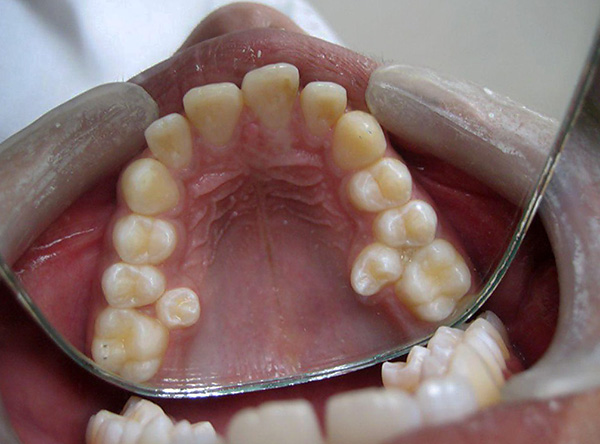

A fotografia abaixo mostra um exemplo de um dente serrado antes da remoção em três partes usando uma broca: